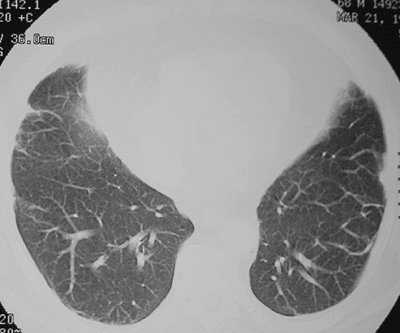

FIGURE 17-14. Chronic PE. CTPA shows a mosaic pattern of lung attenuation. Note diminutive vessels in the areas of hypoattenuated lung.